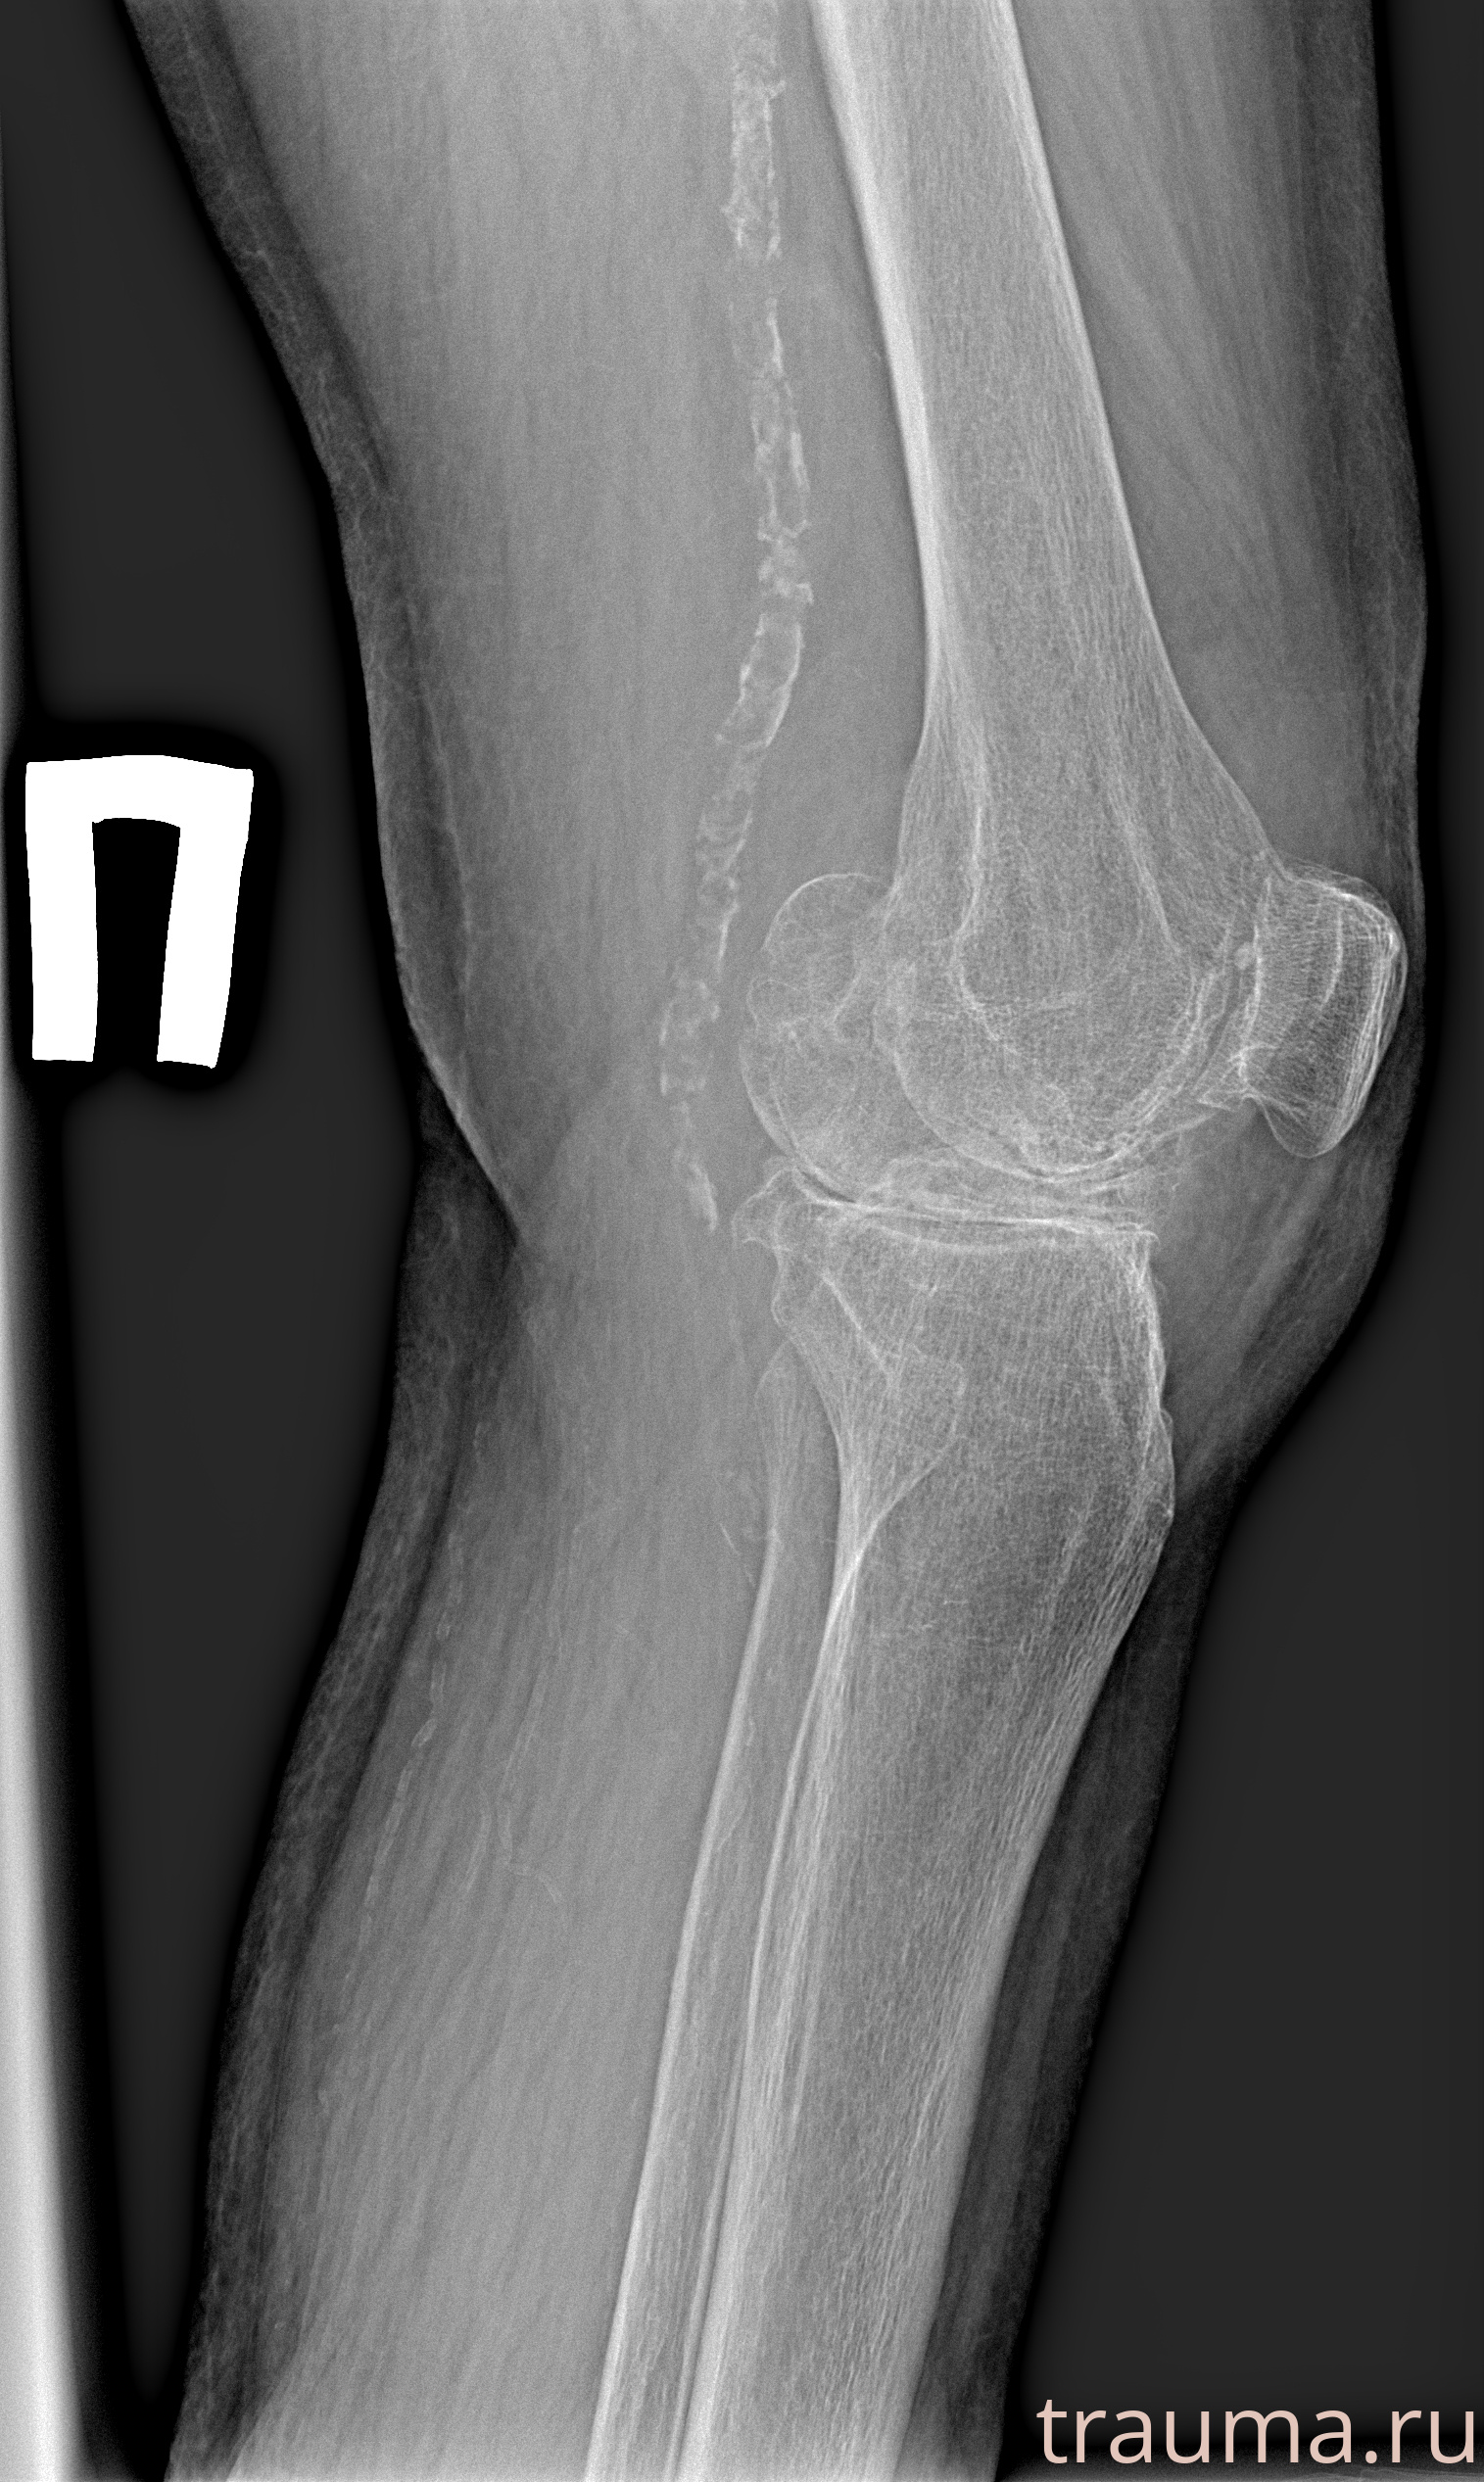

Рентген на дому: по вашему адресу приезжает врач-рентгенолог, травматолог-ортопед с мобильным рентгеновским аппаратом, проводит диагностику травмы или заболевания, делает необходимые рентгенограммы, дает рекомендации по дальнейшему лечению. Получить качественные снимки в домашних условиях возможно благодаря уникальной методике, разработанной МосРентген Центром для института  Склифосовского